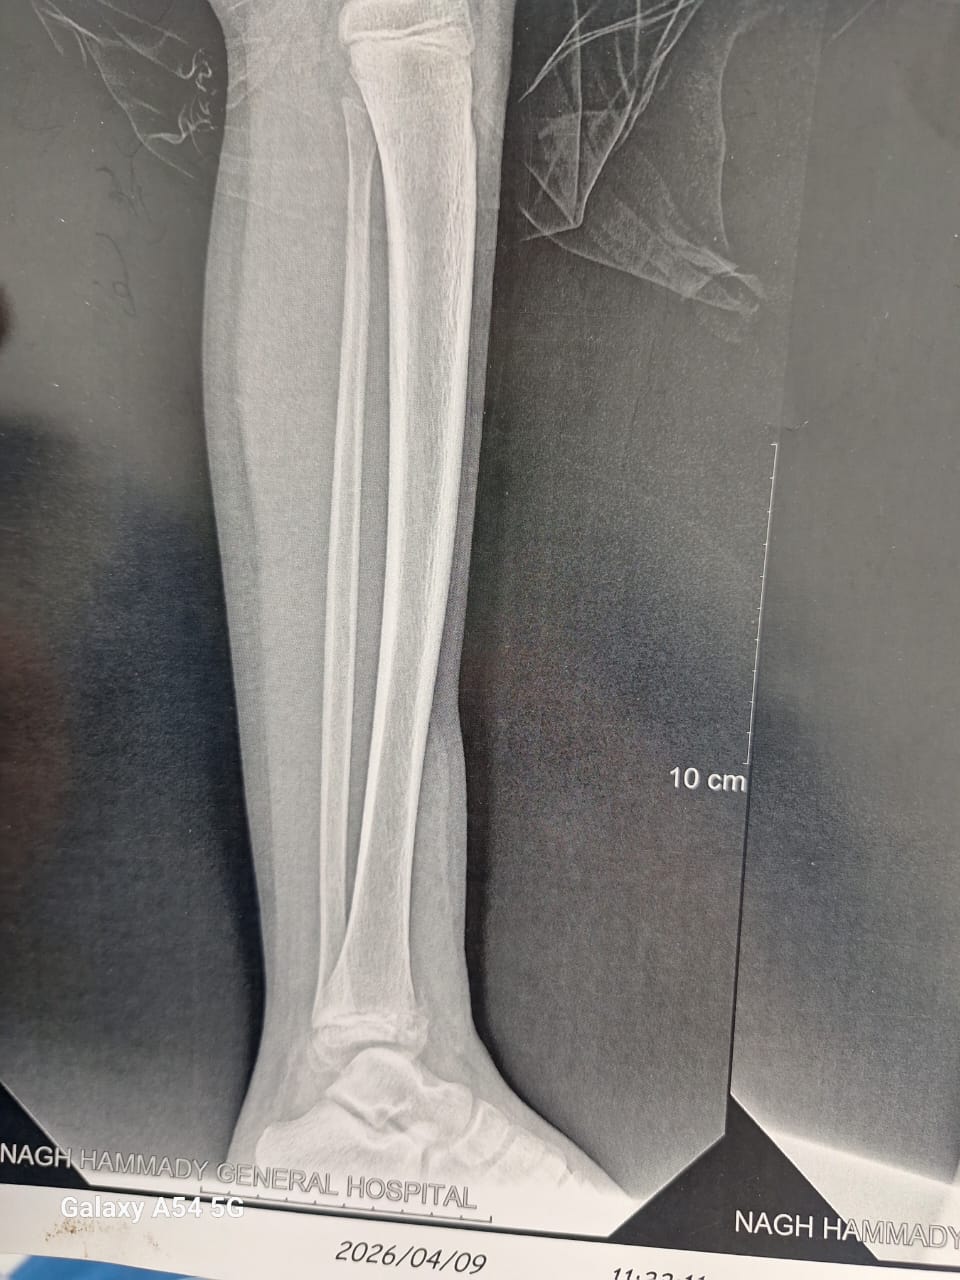

وأضاف مدير المستشفي، أنه تم إجراء 3 عمليات بقسم الأنف والأذن، و3 عمليات بقسم العظام، بالإضافة إلى 4 عمليات جراحية متنوعة، بما يعكس جاهزية الأقسام المختلفة بالمستشفى لتقديم خدمات طبية متكاملة للمرضى